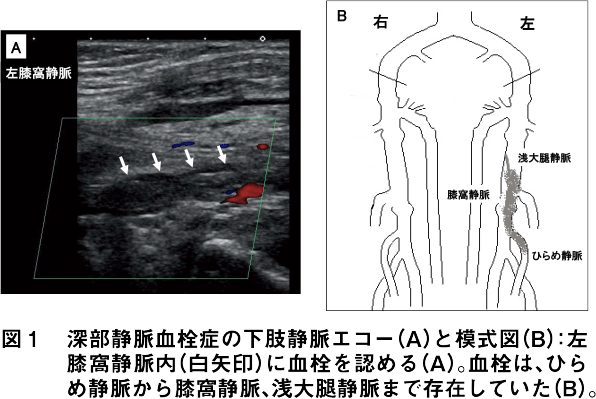

DVTは、深部静脈に血栓ができた病態で、その多くは下肢に認め、左側の発症が右側に比べ多いとされます。膝窩静脈から中枢側に血栓がある近位型(図1)と、血栓が膝窩静脈より末梢側にとどまっている遠位型に分類されます。DVTの多くは下腿にある、ひらめ静脈からできるとされています(図1)。![]()

一方、DVTは下肢のむくみや痛み(特に片側性)をきっかけに病院を受診し、採血のDダイマー上昇からDVTが疑われ、下肢静脈エコー(図1)や造影CTにて診断されることが多いです。![]()